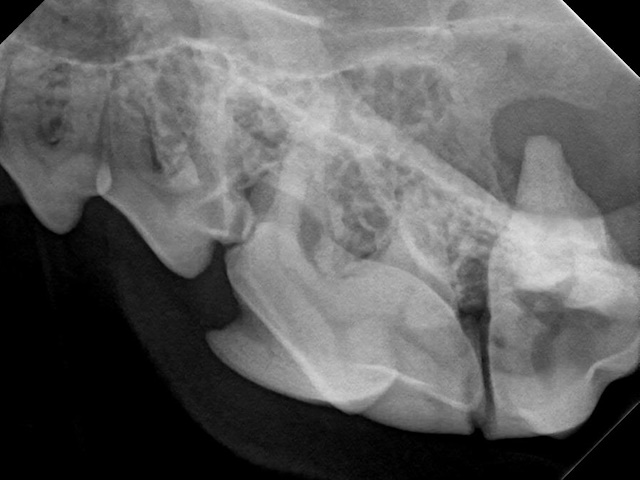

Clinical appearance of the right mandible of a Boxer dog. Notice the first mandibular premolar behind the canine is missing.

Dental radiograph of this area reveals the small, disfigured mandibular first premolar (blue arrow) inside a large bone cyst (highlighted by the yellow arrows).